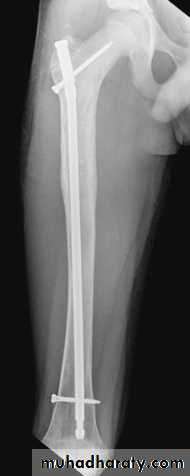

Definitive treatment

closed fractures: by Open reduction and internal fixation, this will decrease the systemic complications.

Fixation of femoral shaft fracture